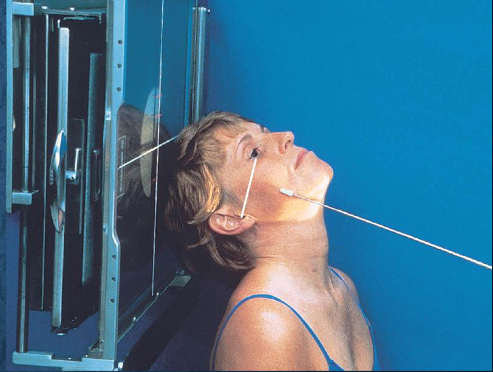

Tangential zygomatic arches

patient position:

upright (seated) or supine (torso elevated)

part position:

hyperextend neck and rest head on vertex

IOML as parallel with IR as possible

rotate MSP of head 15 degrees toward side being examined

tilt top of head 15 degrees away from side being examined

center zygomatic arch to IR

respiration suspended

CR:

perpendicular to IOML

centered to zygomatic arch 1 inch posterior to outer canthus

Tangential zygomatic arches image criteria